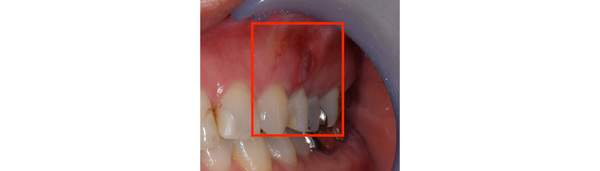

こちらは根の治療の経験がある歯ではありませんが、歯茎が大きく腫れていらした患者様です。レントゲンを撮ってみると原因となっていそうな、2本怪しい歯がありました。過去の虫歯の経緯から後ろの歯の方が怪しいと判断し、1本だけ治療を行いました。

治療後、腫れの大きさの確認のためにCTを撮影すると、上顎洞にまでおよぶ大きな炎症があり、骨が大きくなくなっていることが確認できました。